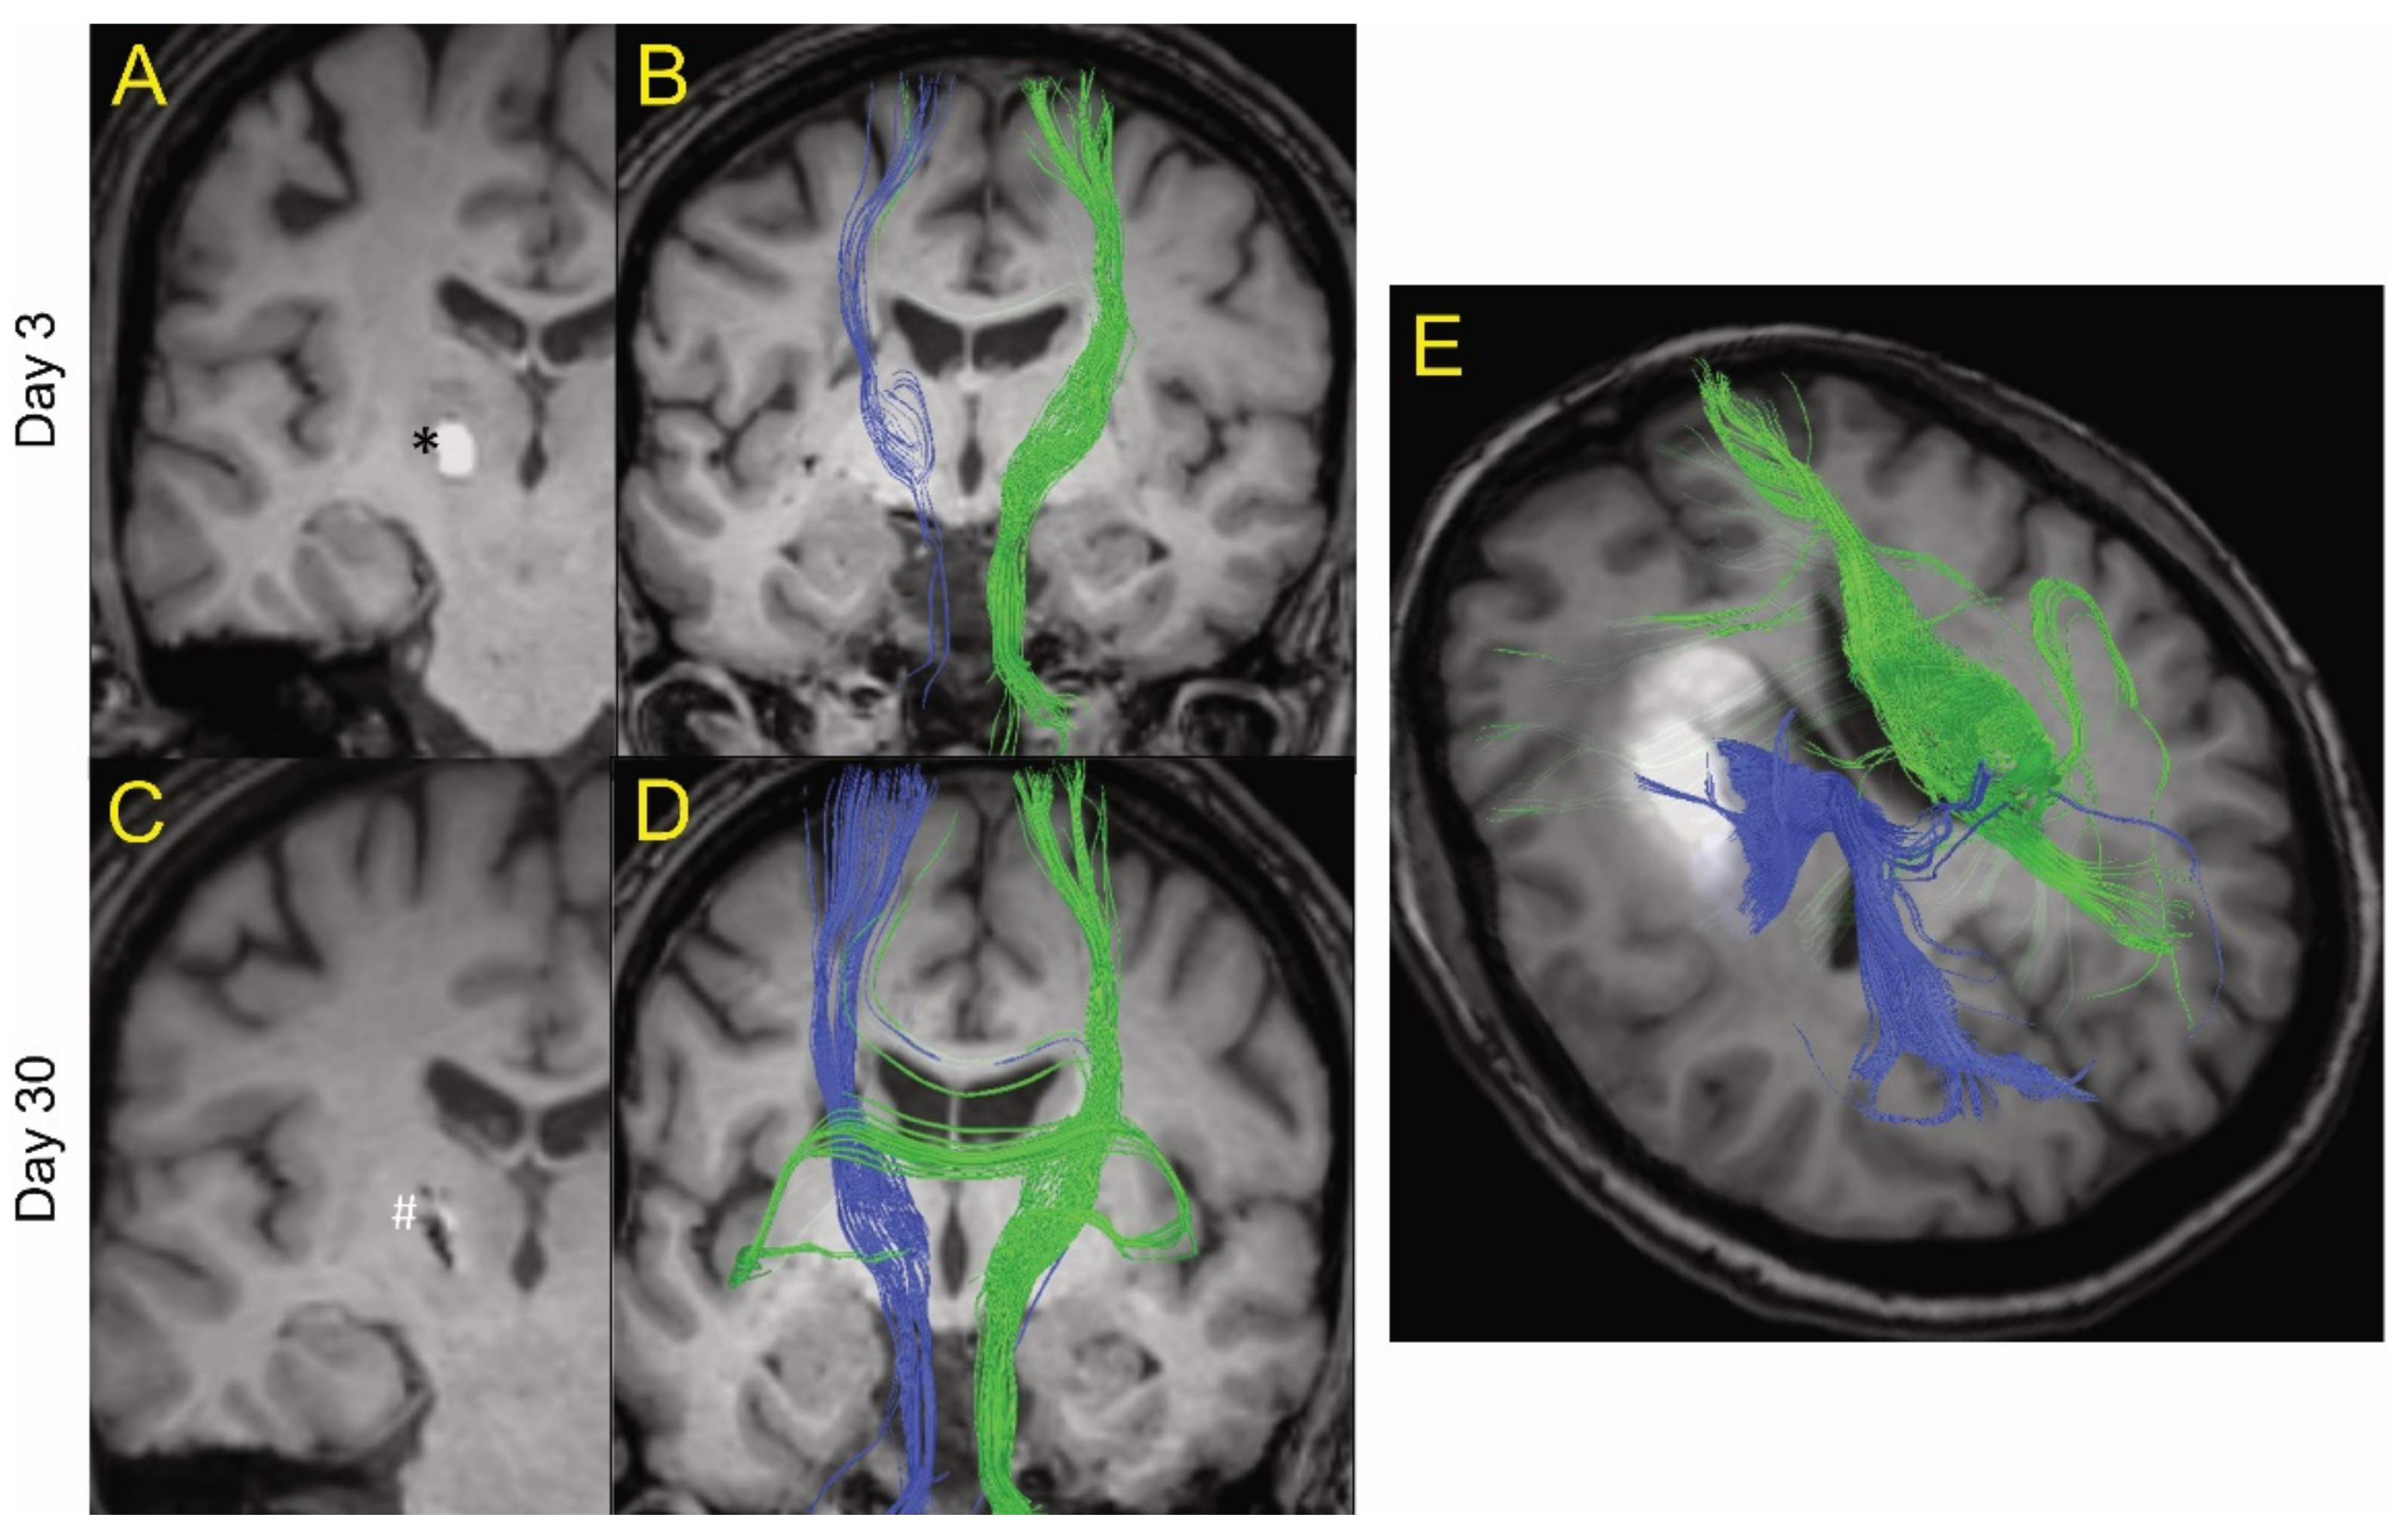

Example of MRI tractography of intracerebral hemorrhage patients. The images are postprocessed 2D axial images with projected WM fibers in 3D in a cranio–caudal direction. One patient (age 50s) is shown at day 3 (A and B) and day 30 (C and D) after ictus. Blue fibers are ipsilateral and green fibers are contralateral to the hematoma. At day 3, there was a general decrease in the fiber tracts (blue) ipsilateral to the hematoma (shown as * in A) compared to contralateral tracts (green). However, there was evidence of some white matter fibers crossing the hematoma. At day 30, the hematoma has largely resolved (shown as # in C) and there was a recovery of the ipsilateral fiber tracts. (E) MRI tractography of a patient (age 60s) with a larger hematoma (19.4 mL) at day 14. It too showed evidence of white matter tracts crossing the hematoma.

Figure 1 shows MRI tractography of two ICH patients. Figure 1A–D show the MRI tractography of a patient (age 50s) with a 0.3 mL hematoma at days 3 and 30 post ictus. At day 3, visually, there was evidence of a reduction in white matter tract fiber density ipsilateral to the hematoma compared to contralateral. Interestingly, some of the visualized ipsilateral WM tracts actually traverse the ICH. By day 30, there was near complete resolution of the hematoma and an apparent recovery of white matter tract fiber density ipsilateral to the lesion as grossly visualized. Figure 1E shows the MRI tractography of a patient (age 60s) with a larger hematoma (19.4 mL) at day 14. It too shows evidence of white matter tracts crossing the hematoma. These results led us to try to quantify the presence of organized white matter (here defined as FA > 0.5) both within the hematoma and around the lesion over time after ictus. The primary goal of the analysis was to analyze the percentage change between two time points for lesion and peri-lesion volume. The authors hypothesize that, in a larger sample of patients, it will be useful to analyze the above data adjusted for covariates like age, gender, and hematoma size; however, given the small sample in our study, this function was thought not to be scientifically meaningful.